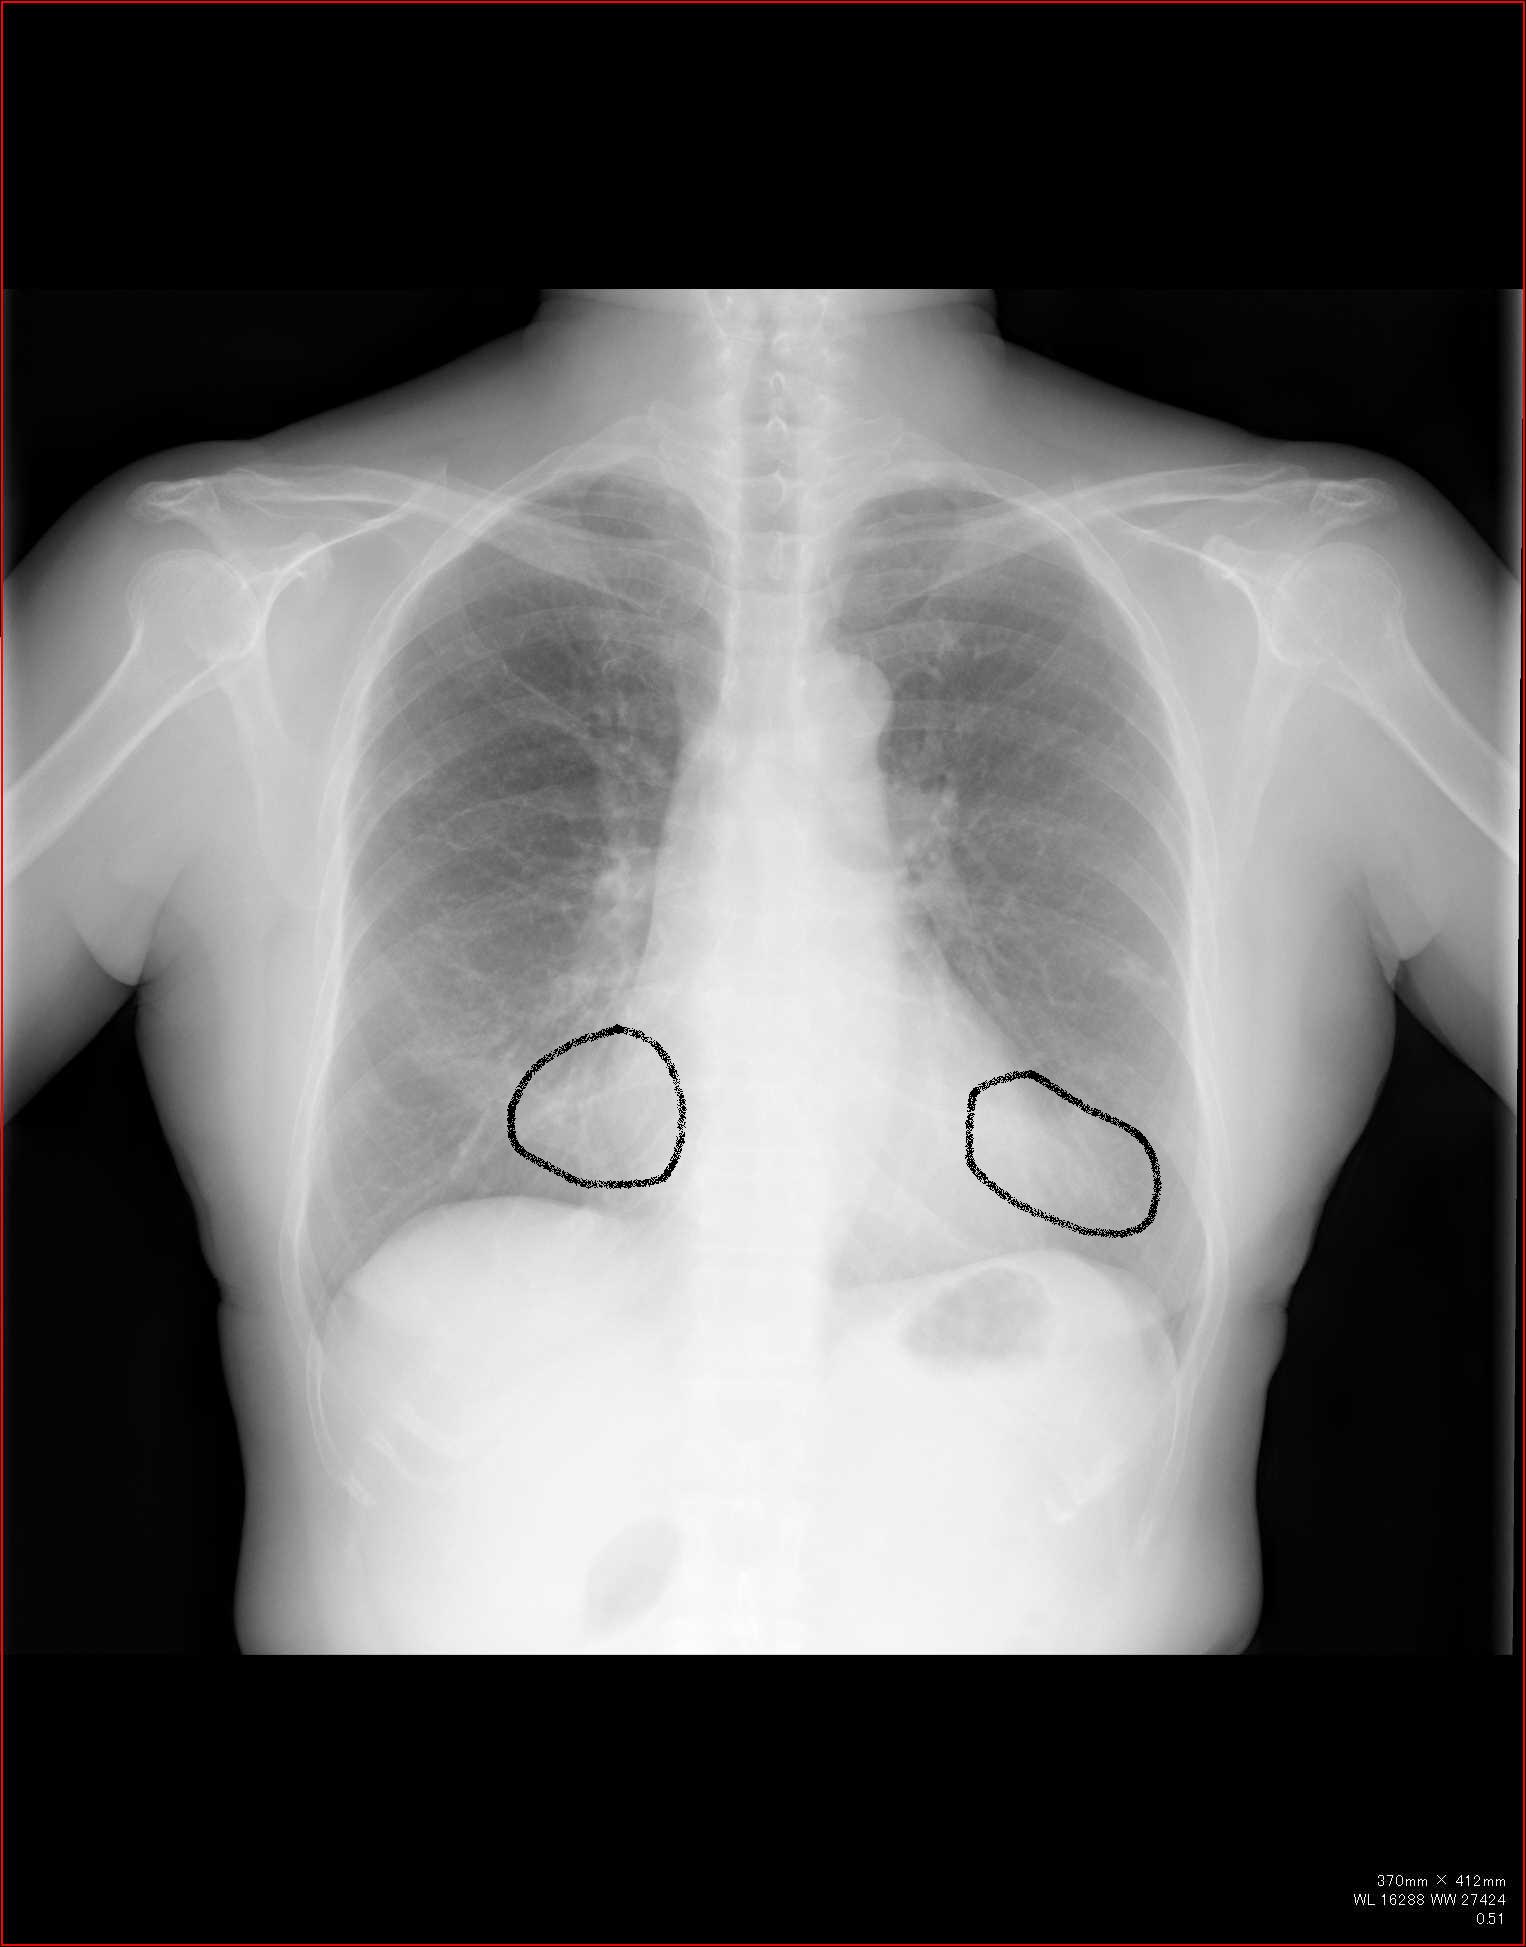

例えば肺の大きさ。

volume

lossや反対に過膨張などの所見は、圧倒的に胸部正面写真がわかりやすいですね。

C縦隔や横隔膜の動きを見る

これらの動きから、肺容量の増減がわかります。